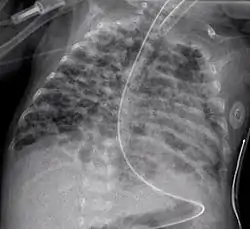

![]() صورة إشعاعية لخلل التنسج القصبي الرئوي صورة إشعاعية لخلل التنسج القصبي الرئوي | |